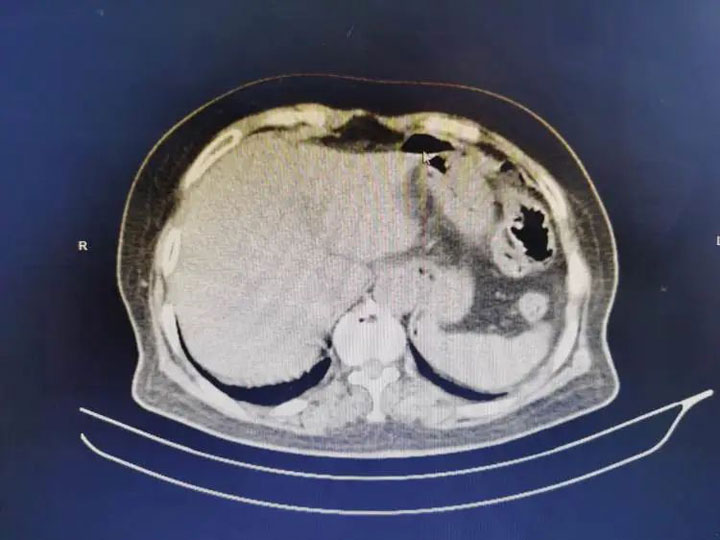

反复上腹部不适20余天后,老人突然出现剧烈上腹部疼痛。1天后腹痛难忍的她被家人送入广济医院急诊科,结合腹部体征和腹部立位平片CT等,确诊其系消化道穿孔。完善检查和准备后,在手术室卜美林主任及其团队的麻醉监护下,普外科代坤主任带领团队立即为其急诊行“腹腔探查+腹腔脓液冲洗引流+胃溃疡穿孔修补术”,手术顺利结束,目前老人恢复良好,已正常流质饮食。

代坤主任解释道:“患者系胃窦部穿孔,消化道穿孔也是临床最常见的外科急腹症之一。突发上腹部剧烈疼痛,尤其是进食后疼痛迅速波及全腹的情况,一定要警惕,及时的救治能很大程度的降低重症感染情况和死亡率。该病好发于中老年人,胃或者十二指肠内容物外溢至腹腔,会引起腹膜炎、休克、脓毒症等,造成脏器功能受损,6—8小时即可发展为化脓性腹膜炎,起病急、进展快、病程重,死亡率高达20%。所以及早诊断和有效治疗,对于挽救患者生命、改善预后至关重要。”随着胃肠镜检查的广泛应用,消化系统疾病的早筛早诊更加便利,对此代坤主任建议做好日常健康管理,避免急腹症等情况发生。